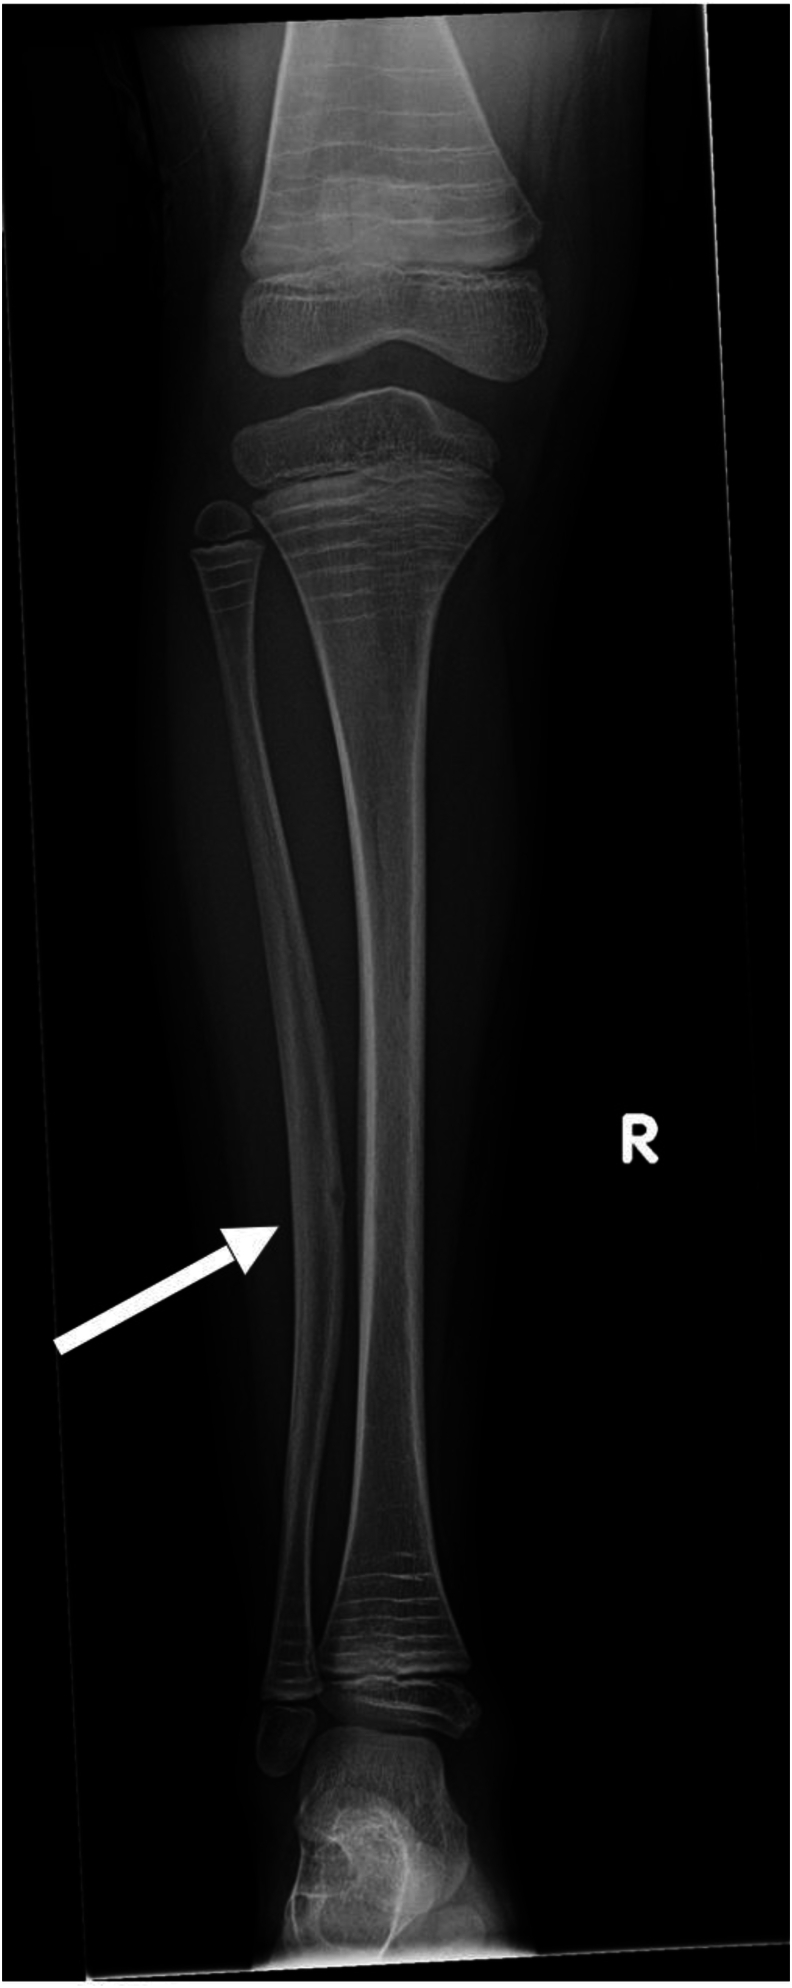

Background: Osteogenesis imperfecta (OI), a rare genetic disorder of collagen synthesis and metabolism, is characterized by cortical bone thinning and decreased trabecular bone. We have noted individuals with OI develop radiolucent lesions in the cortices of the long bones and these have not been previously described. The prevalence of these lesions in the long bones of children and the significance of their appearance in relation to subsequent fractures is unknown.

Results: Lesions were present in 55 (17%) of the 328 patients. A total of 89 lesions were identified in these 55 patients, with 138 positive radiographs across the OI subtypes. Of the 138 positive radiographs, lesions were present in 90/138 (65%) tibiae, 10/138 (7%) fibulae, 24/138 (17%) femora, 4/138 (3%) ulnae, 1/138 (1%) radius, and 9/138 (7%) humeri. In affected patients, there was an average of 1.62 lesions per patient. In 99% (136/138) of the radiographs, the lesion was present on the diaphysis of the long bone, and in 86% (119/138) of the x-rays, the lesion was located on the tension side. 64% (57/89) of the lesions developed after a previous fracture, and in 24% (21/89) of lesions, a fracture subsequently occurred through the area of the lesion.

Conclusions: We present that radiolucent lesions of long bone diaphyses are a characteristic finding in OI and often presage fractures.

Key concepts: (1)Radiolucent lesions are a characteristic finding of OI and have not been yet described in literature.(2)These lesions may represent a probable failure of ossification and lack of remodeling in the area of the lesion.(3)There is no clear etiology of this finding, although many arise in areas of prior fracture or osteotomy.